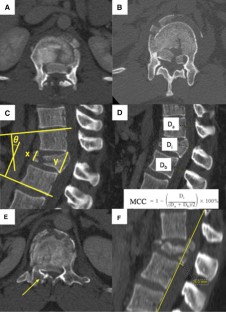

Fig. 1